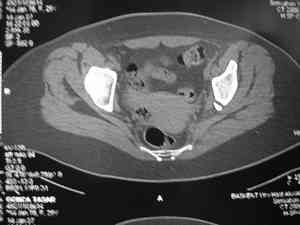

Обследование дополнительными снимками: прямая, инлет и оутлет, а КТ срезы покажет имевшиеся мозольные перемычки и истинное смещение в крестцово подвздошном сочленении.

Дорогой Андрей. Мы имеем дело с комбинированной (ротационно и вертикально) нестабильностью таза со смещением правого гнемипелвиса. При таких переломах, фиксация только переднего полукольца вне зависимости от метода фиксации, как уже было сказано Djoldas Kuldjanov, M.D., не может создать адекватной фиксации. И перелом пластины был вполне ожидаемым после активизации пациента. Смещение сохраняется, и по-видимому не 2 см., а все 4, если не более. Разница всего (+2 см) по конечностям как вы указываете, скорее скомпенсировано позвоночником и протезом. Дополнительные снимки или КТ исследование помогли бы уточнить степень смещения с точностью до мм., выявить перелом поперечного отростка пятого поясничного позвонка, или помимо разрыва правого крестцово-подвздошного сочленения выявить перелом боковой массы крестца справа и т.д. При возможности, конечно, все это желательно сделать. Но мало что изменится с практической точки зрения, т.к. задача - это низведение репозиция и надежная фиксация правого гемипелвиса. Учитывая плачевный опыт стержневого аппарата, давность травмы совершенно очевидно, что поставленная задача достижима при открытой репозиции и одномоментной фиксации переднего полукольца с артродезированием правого крестцово-подвздошного сустава. Операция выполняется в положении больного на здоровом боку или полубоку из расширенного трансоссального подвздошно-пахового доступа с переходом на лонное сочленение доступом по Pfannenstiel. Указанный доступ обеспечивает подход к крестцово-подвздошному сочленению как спереди так и сзади. После артродезирования выполняется синтез лонного сочленения. Клинический пример

закрыто или открыто, а позволит ли Вам это сделать оссифицированная связка? Без подробного КТ лечение застарелой травмы таза обречение пациента и врача на множество неприятных и "неожиданных" открытий.

Доведите диагностический процесс до конца (КТ, функциональные снимки я уж не говорю про сандартные Outlet и inlet), поищите другой источник болей (поясница например).